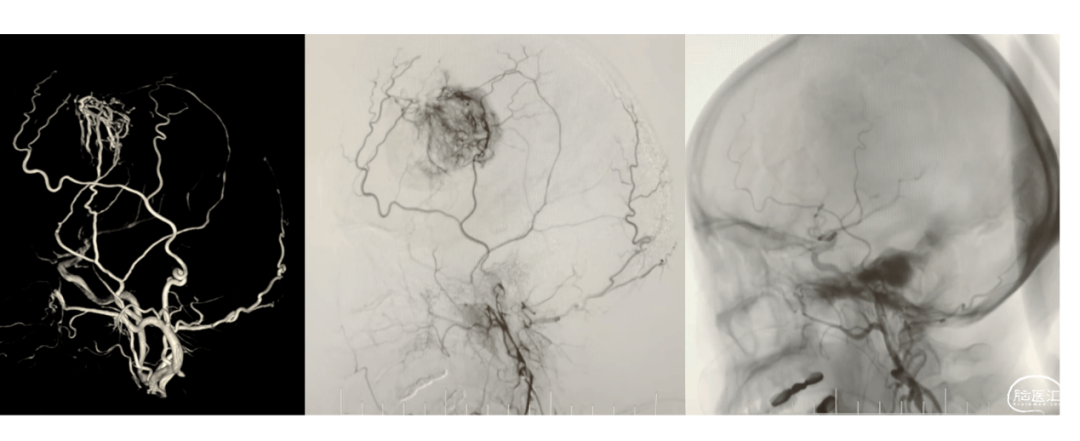

9

复合手术技术切除颅内富血供肿瘤是一种安全、有效的治疗方法,在复合手术室,通过先介入栓塞+然后切除肿瘤的模式,可“一站式”切除颅内富血供的肿瘤,为颅内复杂的富血供肿瘤的治疗提供了新的选择,该技术不仅显著降低了手术风险,还提高了手术成功率。